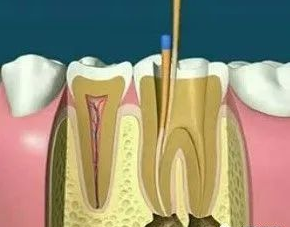

01、什么是根管調(diào)節(jié)?根管調(diào)節(jié),也稱為牙髓調(diào)節(jié),是調(diào)節(jié)牙髓疾病和根尖周疾病的有方法。通過(guò)去除根管中的炎性牙髓和壞死物質(zhì)并進(jìn)行適當(dāng)?shù)南?,填充根管以消除根管?nèi)容物對(duì)根尖周圍組織的不利刺激,防止根尖周病變的發(fā)生或促進(jìn)根尖周愈合病變。此操作可保護(hù)牙齒,因此可與拔牙互補(bǔ)。根管調(diào)節(jié)很麻煩,通常需要2-4次就診才能完成,并且患者會(huì)遭受更多的痛苦。

6、根管充填:封閉整個(gè)根管系統(tǒng)、堵塞主根管和側(cè)副根管出口、防止微生物和液體的滲漏。無(wú)論是側(cè)方加壓法還是垂直加壓法,應(yīng)做到根管充填致密,根管充填后X線片上無(wú)根管腔隙,也不能超出根尖孔。

7、根管打樁:因牙體缺損過(guò)多,導(dǎo)致牙的強(qiáng)度(承受力量的性能)大幅度下降,不能很好地承受咀嚼力量。打樁的目的是增加牙根及牙冠的強(qiáng)度,增加患牙的穩(wěn)固。